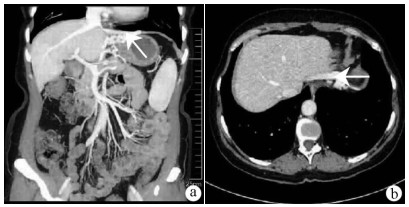

Expert consensus on the imaging diagnosis of hepatic echinococcosis

Radiology of Infection Sub-branch, Radiology Branch, Chinese Medical Association, Committee on Radiology of Infectious, Radiology Branch, Chinese Medical Doctor Association

2021, 37(4): 792-797. DOI: 10.3969/j.issn.1001-5256.2021.04.014

Abstract(1244) HTML (604) PDF (2065KB)(121)

Abstract:

Echinococcosis is a zoonotic disease with global distribution and has become an issue seriously affecting public health around the world. Imaging technology plays an important role in the early diagnosis, preoperative evaluation, and treatment outcome monitoring of hepatic echinococcosis. At present, no consensus has been reached on the imaging diagnosis of echinococcosis, which brings difficulties in the learning and training of imaging professionals and the standard diagnosis and treatment of echinococcosis in clinical practice. For this reason, Beijing YouAn Hospital, Capital Medical University, and The First Affiliated Hospital of Xinjiang Medical University organized the radiologists engaged in infection and inflammation from several hospitals to reach a consensus on the basis, principles, and criteria for the imaging diagnosis of echinococcosis and the differential diagnosis of echinococcosis, with reference to international guidelines, related articles, the latest research findings in China and globally, and the methodological requirements for the establishment of guidelines and standards in evidence-based medicine, so as to provide a clear diagnostic basis for clinicians in the clinical application of hepatic echinococcosis imaging.